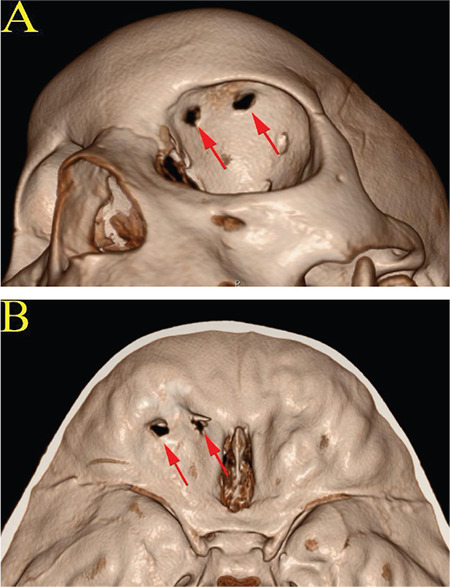

一名 4 岁男孩被一只大型犬刺伤左眼眶,随后被转诊到我们的三级医院。当时流泪增多,原以为是炎症反应所致。然而,研究人员发现,泪液在反滕卧位和做瓦尔萨尔瓦动作时会增多。光环征和β转铁蛋白试验均呈阳性,因此诊断为脑脊液(CSF)瘘,患者接受了眶上开颅手术。手术中发现了硬脑膜撕裂并进行了适当缝合,然后在撕裂处应用了纤维蛋白胶和自体硬脑膜移植。术后脑脊液渗出停止,随访 10 天后患者出院。在 4 年的随访中,患者没有再出现 CSF 渗漏。虽然 CSF 渗漏很少见,而且可能很难从流泪中辨别出来,但如果出现气胸和晕轮征,则应考虑瘘管修补术。

A 4-year-old boy was referred to our tertiary hospital after a penetrating adnexal injury by a large-breed dog to the left orbital area. There was an increase in lacrimation, which was thought to be due to an inflammatory reaction. However, it was discovered that the lacrimation increased in the reverse-Trendelenburg position and with the Valsalva maneuver. Halo sign and beta transferrin test were positive, which led to the diagnosis of cerebrospinal fluid (CSF) fistula, and the patient was operated using a supraorbital craniotomy. A dural tear was visualized and sutured appropriately, then fibrin glue and an autologous galeal graft were applied to the tear. The CSF oculorrhea stopped postoperatively, and the patient was discharged after 10 days of follow-up. The patient had no recurrent CSF leakage at 4-year follow-up. Although CSF oculorrhea is rare and may be difficult to discern from lacrimation, the presence of pneumocephalus and halo sign should suggest fistula repair.